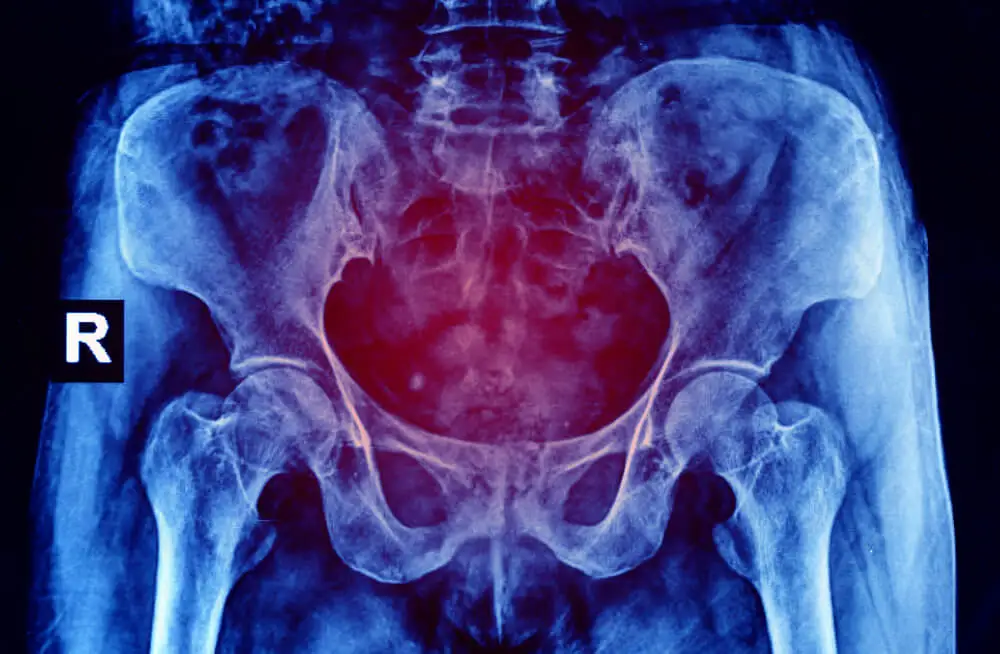

La sinfisiotomía es una operación en la cual se cortan parcialmente las fibras que unen los huesos del pubis, en zona anterior de la pelvis. Es decir, se dividen parcialmente las fibras de la sínfisis pubiana para separar la articulación y aumentar la dimensión de la pelvis.

El objetivo de la sinfisiotomía es ampliar la dimensión de la pelvis y así facilitar el paso del bebé a través del canal del parto. Esto se hace necesario, por lo general, cuando el feto es muy grande para pasar normalmente a través de la pelvis.